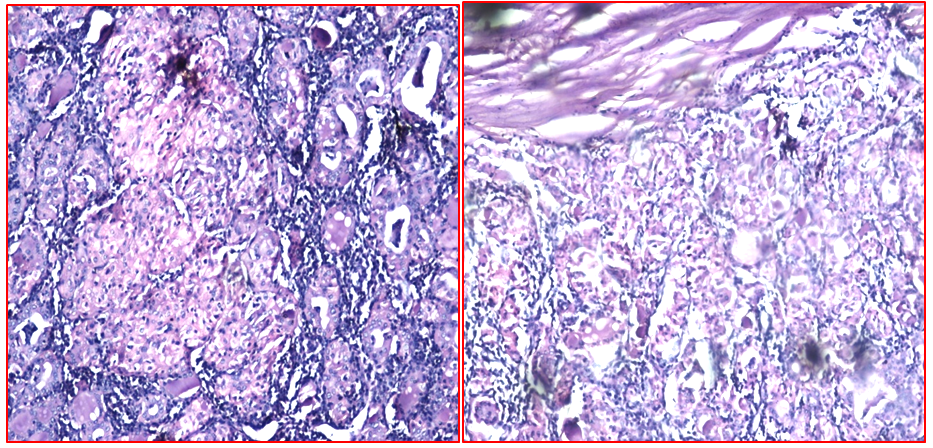

Figure 8 Ductal carcinoma in situ HPE, H&E x10.

Figure 9 Ductal carcinoma in situ on frozen section X10.